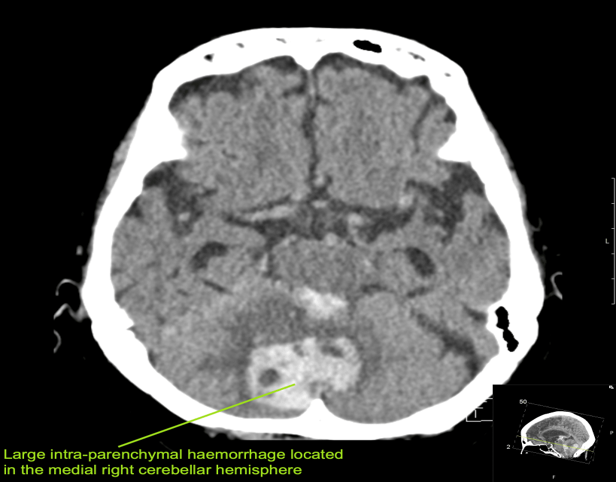

CASE 4 –An 82-year-old female of Asian descent from a nursing home presents with hypertension, nausea and vomiting. Vitals are BP 180/105, HR 65, GCS 8, which soon dropped to 6. Patient is K/C/O atrial fibrillation and is on warfarin. soon after arrival, warfarin was reversed due to suspicion of intracranial hemorrhage and the patient was sent for urgent CT scan.

EXPLANATION –There is a large intra-parenchymal hemorrhage located in the medial right cerebellar hemisphere extending into the cerebellar vermis. There is intraventricular extension into the fourth ventricle and aqueduct with mild obstructive hydrocephalus (mild dilatation of the lateral ventricles).